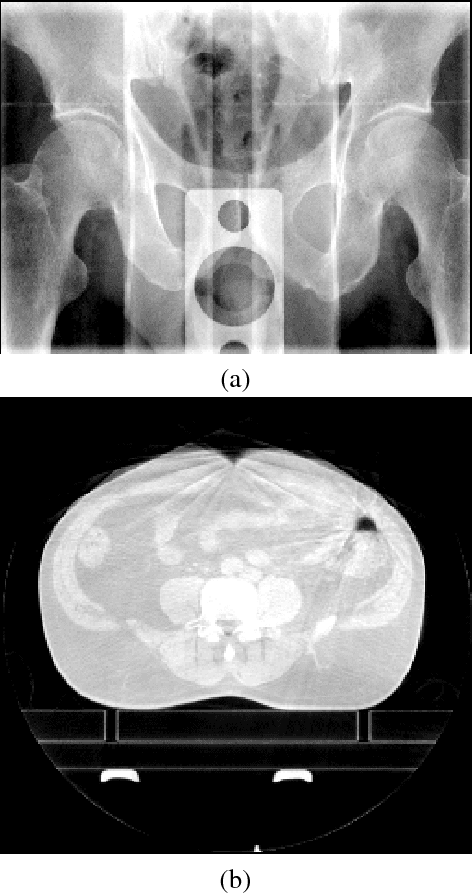

Abstract:High-frequency noise is present in several modalities of medical images. It originates from the acquisition process and may be related to the scanner configurations, the scanned body, or to other external factors. This way, prospective filters are an important tool to improve the image quality. In this paper, we propose a non-local weighted operational anisotropic diffusion filter and evaluate its effect on magnetic resonance images and on kV/CBCT radiotherapy images. We also provide a detailed analysis of non-local parameter settings. Results show that the new filter enhances previous local implementations and has potential application in radiotherapy treatments.